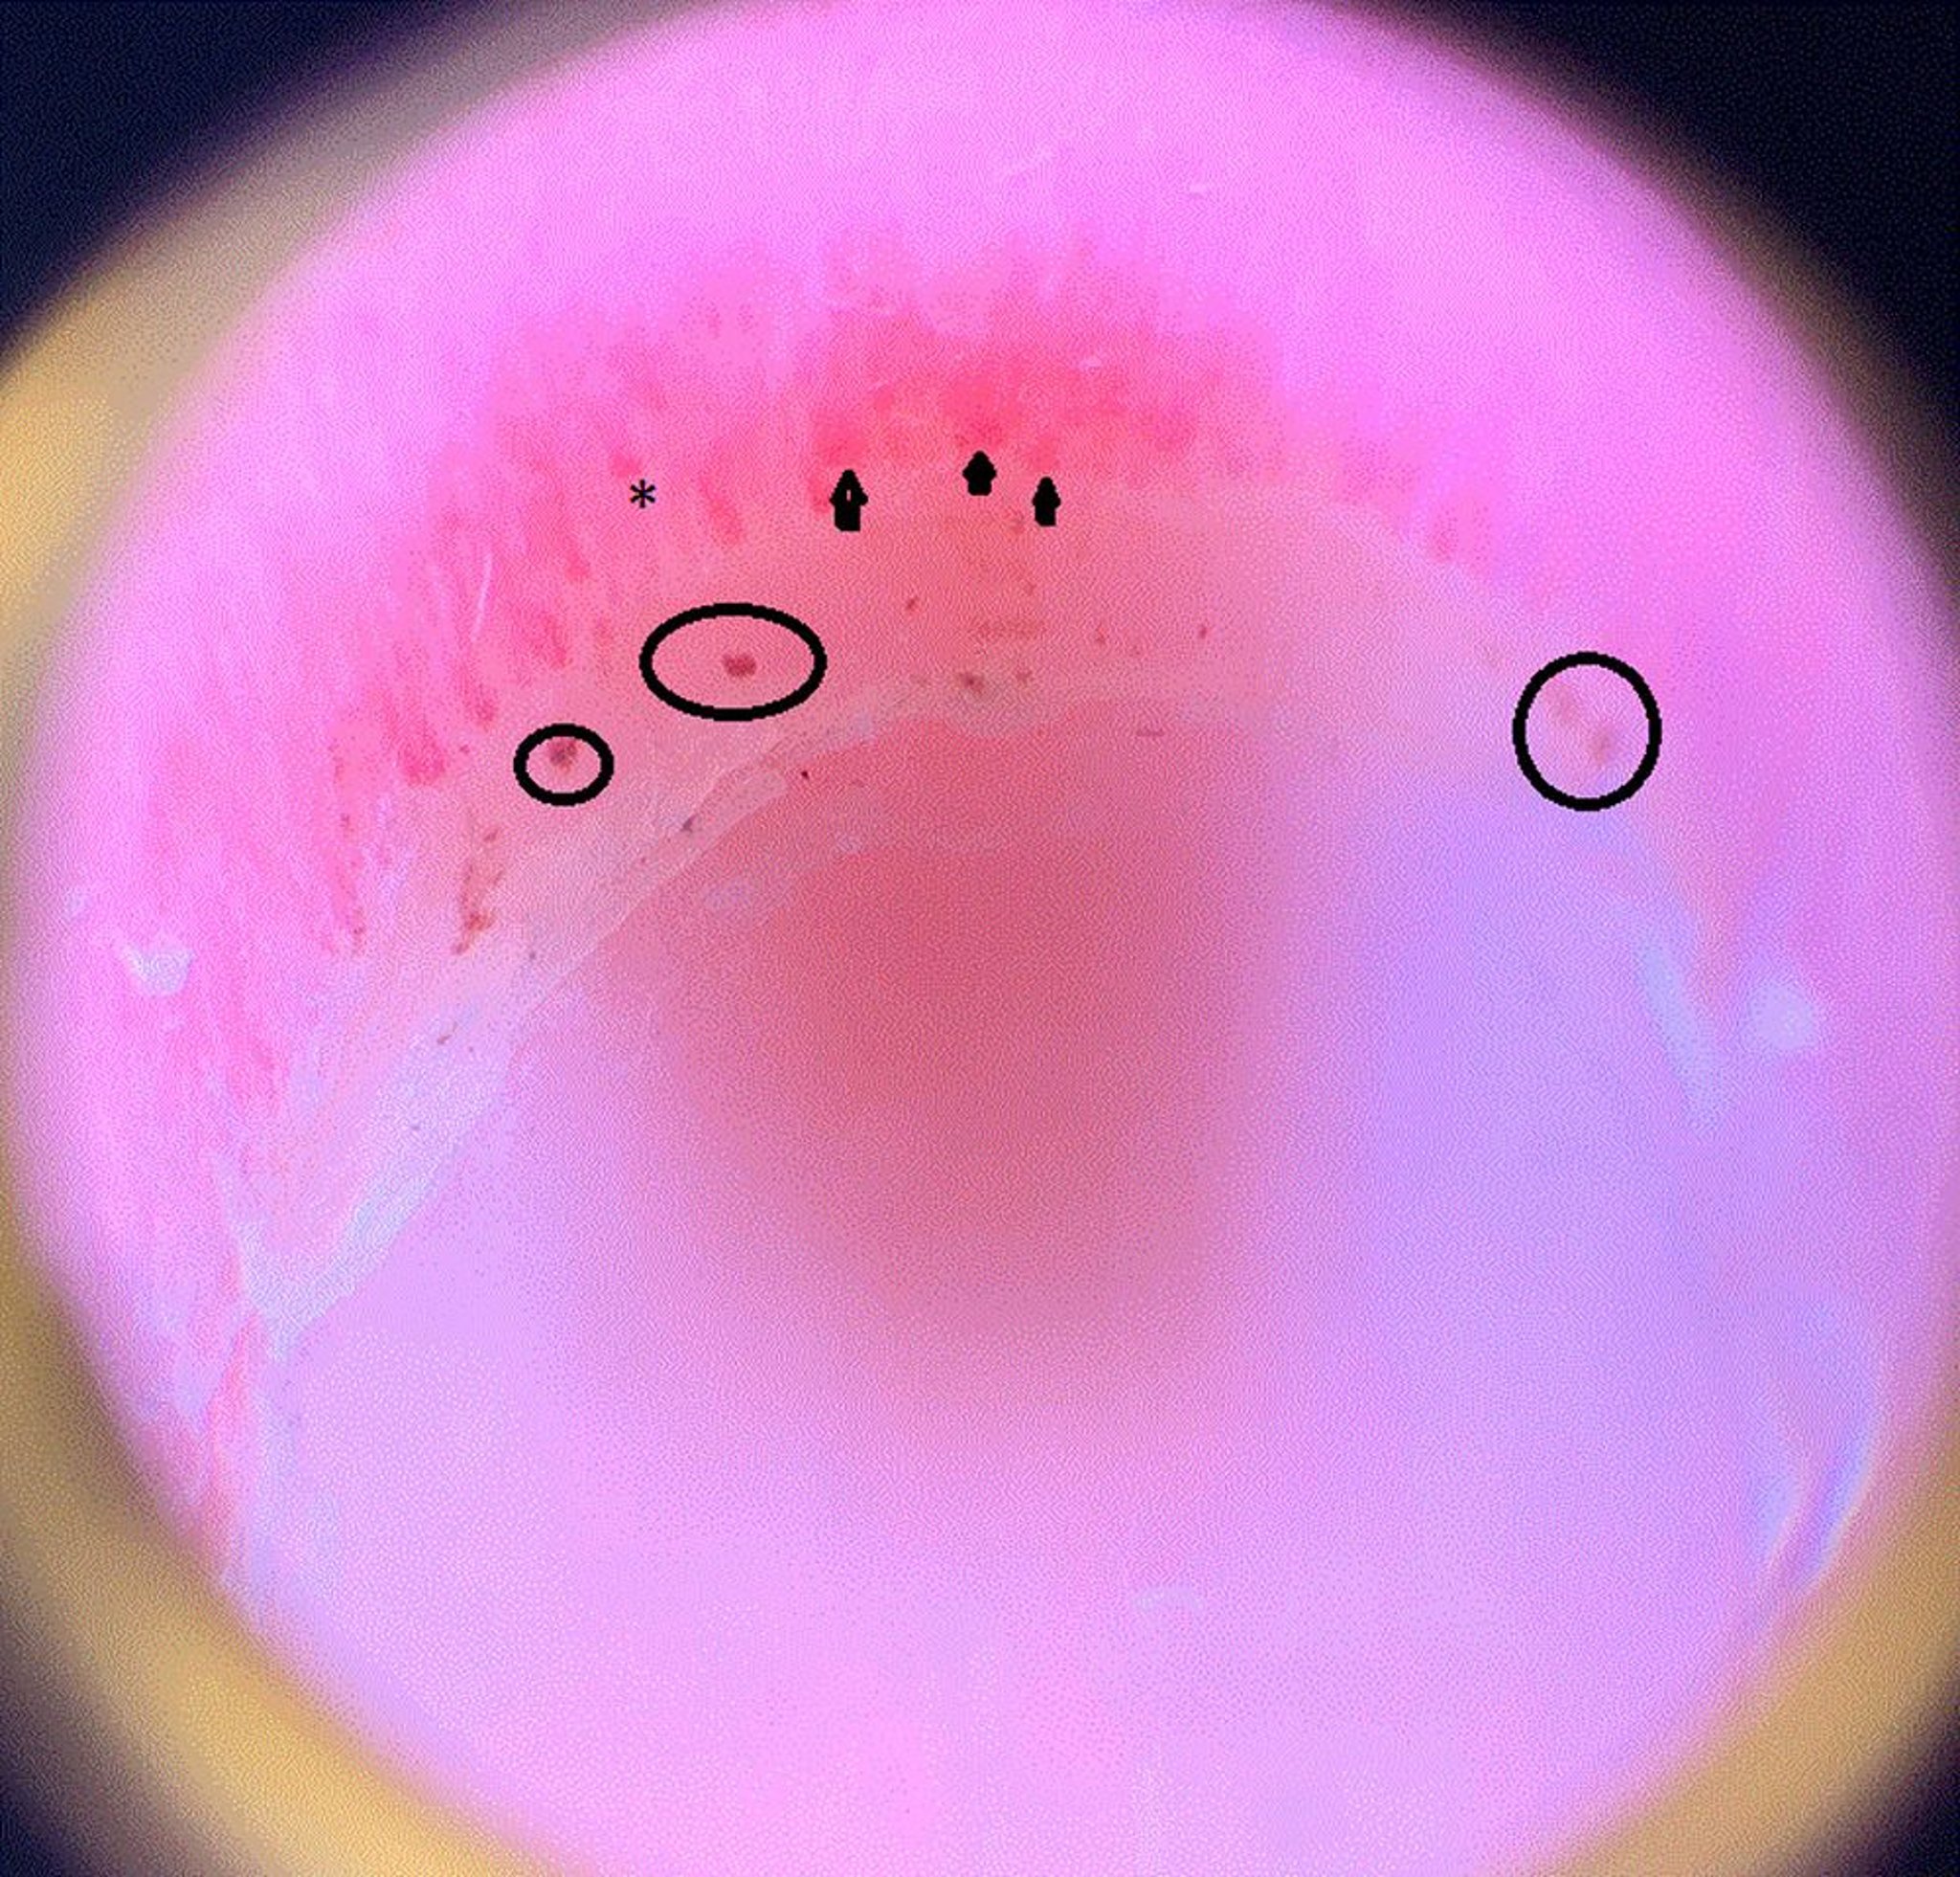

Questa immagine mostra anse capillari dilatate (punte di freccia), un'area di retrazione, il che significa che il capillare termina prematuramente e si ritira e quindi appare più corto degli altri (asterisco), e emorragie periungueali (cerchi) nella plica ungueale di un paziente con sclerosi sistemica.

Image courtesy of Sanjeev Patil, MD.